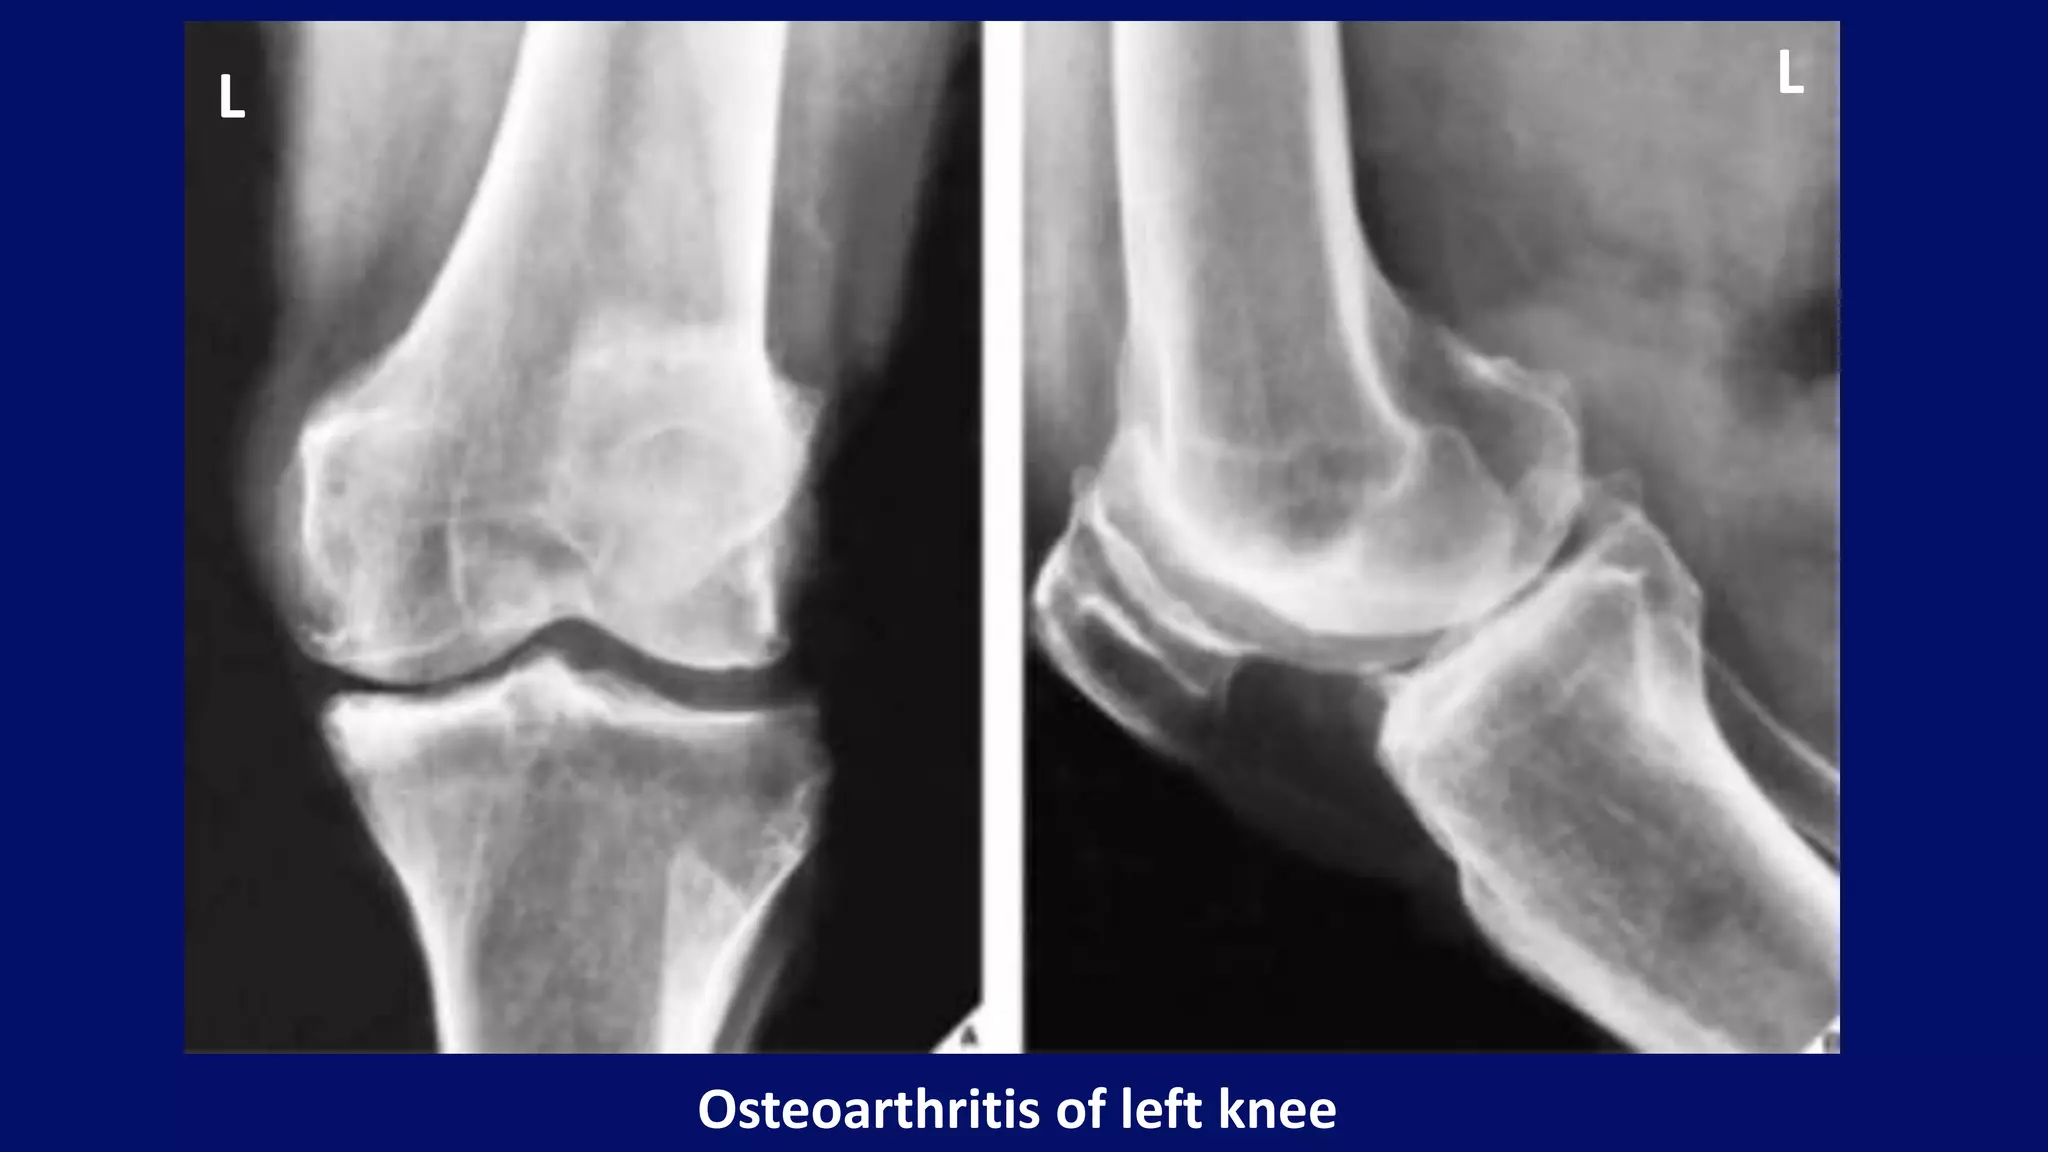

Osteoarthritis of left knee

L L

AP and lateral

both knee

radiographs

bilateral knee

osteoarthritis.

• #23 Anteroposterior (A) and lateral (B) projections of the knee of a 57-year-old woman demonstrate narrowing of the medial femorotibial and femoropatellar compartments, subchondral sclerosis, and osteophytosis, which are the typical features of osteoarthritis. Note that osteophytes that were not obvious on the frontal projection are much better-demonstrated on the lateral radiograph.